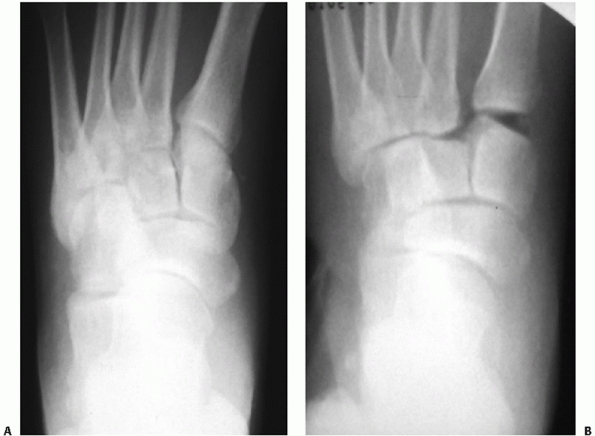

![]() |

FIGURE 60-26 Anteroposterior view of the tarsometatarsal joint. A. Normal joint alignment on weight-bearing view. B.

Manual stress view of tarsometatarsal injury with lateral migration of first and second metatarsals while foot is non-weight bearing. |

FIGURE 60-27 Medial oblique view of the tarsometatarsal joint. A. Normal fourth tarsometatarsal joint alignment on weight-bearing view. B.

Non-weight-bearing view of tarsometatarsal injury with lateral displacement of fourth metatarsal in relation to the medial border of the cuboid (shown by arrows). |